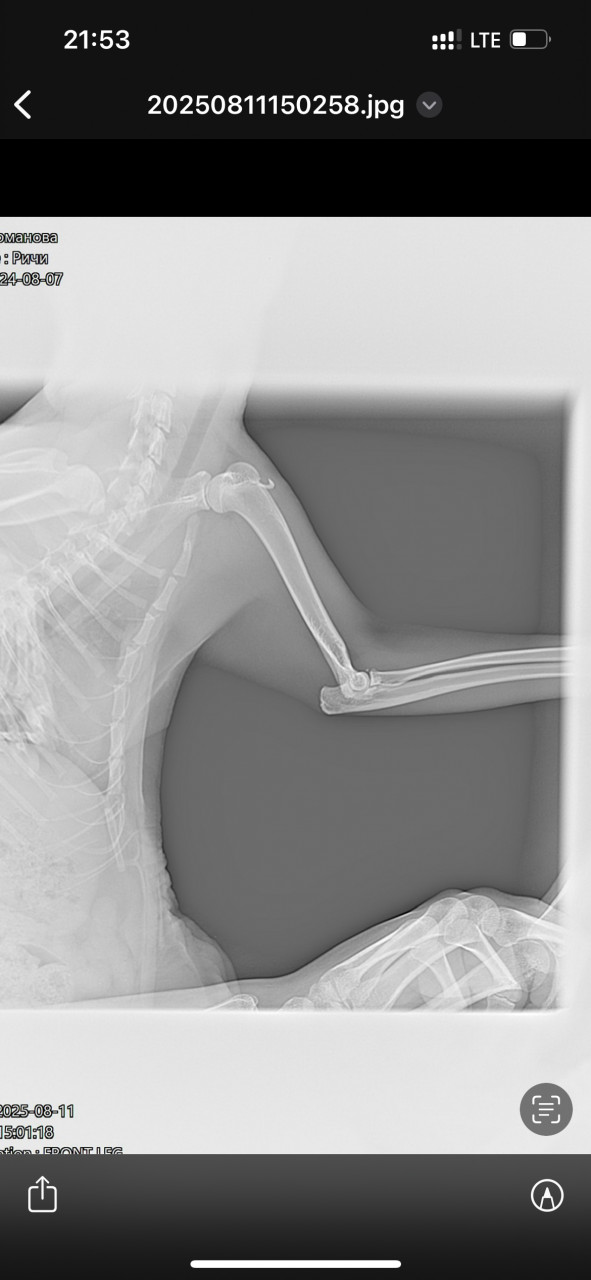

11.08 увидела, что он хромает, поехали на ренген. Сделали 3 снимка-без описания. Сказали колоть флексоарофен 0,3 в течении 3-5 дней. 17 числа опухла лапка в районе подушечки на левой ноге. Врач сказал колоть больше нельзя флексопрофен. 18 сегодня лапка не опухает, немного на неё наступает кот, до этого прыгал. Врач назначил Бонхарен или аналоги, нашла Хиовет в дозе 0,37 на его вес. Уточните, по снимку, что у кота? Стоит ли колоть Хиовет сейчас или подождать немного? Или вопрос к врачу ортопеду?

Здравствуйте. По рентгеновским снимкам у вашего кота отмечается перелом в области предплечья (лучевая и локтевая кости) с нарушением целостности и смещением. Это серьезная травма, которая требует консультации ветеринарного хирурга-ортопеда. Самостоятельно только противовоспалительными препаратами или хондропротекторами (Бонхарен, Хиовет) проблему не решить т.к нужна фиксация (операция или жесткая иммобилизация).